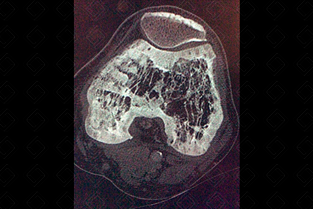

Texto alternativo para a imagem Figura 1. Créditos: Dra. Elazir Mota - Rio de Janeiro/RJ

Descrição da figura 1: Radiografia do fêmur em paciente portador de doença de Paget. Observar o trabeculado ósseo grosseiro na região metadiafisária, o espessamento cortical (asterisco) e as fraturas em banana – fraturas horizontais (setas vermelhas).

A doença de Paget pode ser dividida em três fases radiológicas: lítica , na qual predomina a reabsorção óssea pelos osteoclastos, mista e sua fase final , blástica.

• Na fase final ou blástica, observam-se áreas de esclerose e aumento do volume ósseo. Nesta última fase da doença, devido à excessiva deposição de osso "anormal", há uma grande predisposição a fraturas, como as características fraturas em banana (figuras 1 e 2). As múltiplas fraturas e o remodelamento ósseo anormal acarretam nas deformidades ósseas. Na calota craniana, há espessamento da tábua interna, levando ao aumento do espaço diploico ( Tam O`Shanter - boina escocesa), podendo acarretar em sintomas neurológicos. Na coluna, o excessivo remodelamento leva ao surgimento da vértebra em marfim , podendo haver aumento volumétrico do corpo vertebral e seus elementos posteriores.